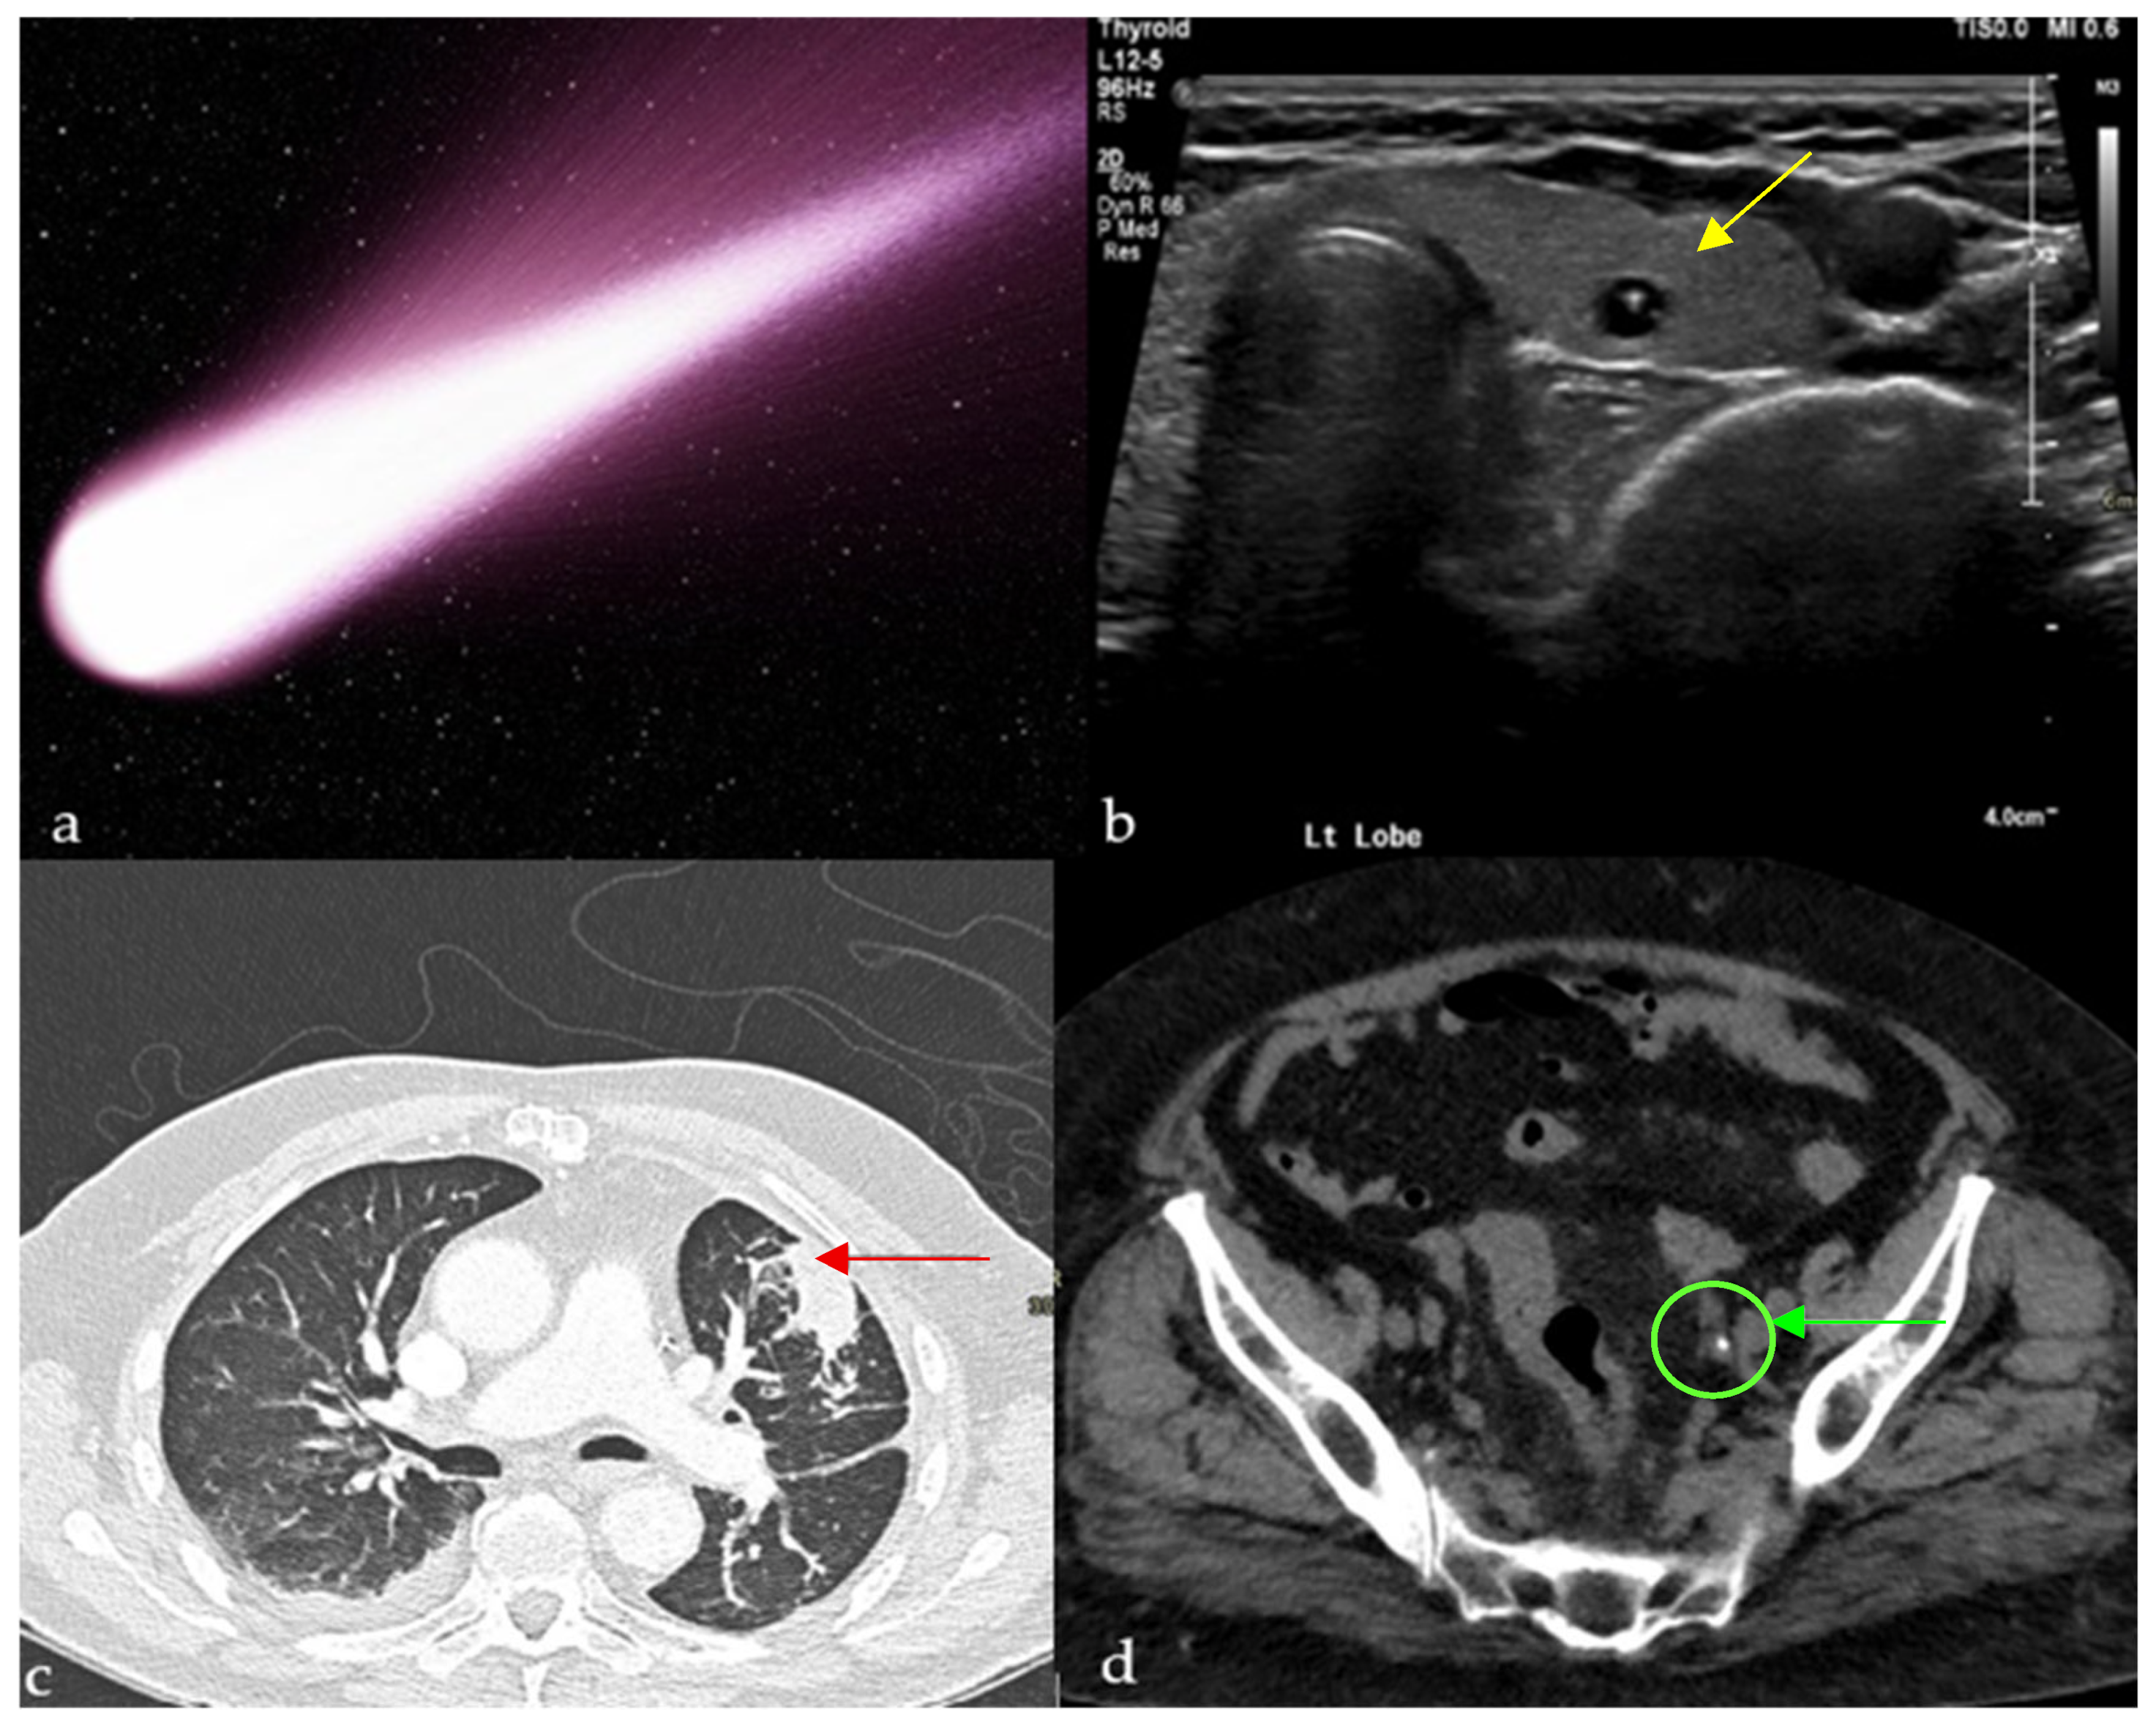

2.1. Comet-Tail Artifact

2.1.1. On Ultrasound (US)

2.1.2. On Computed Tomography (CT)

Chest

Abdomen and Pelvis

- Shapiro, R.S.; Winsberg, F. Comet-tail artifact from cholesterol crystals: Observations in the postlithotripsy gallbladder and an in vitro model. Radiology 1990, 177, 153–156. [Google Scholar] [CrossRef]

- Oh, S.H.; Han, H.Y.; Kim, H.J. Comet tail artifact on ultrasonography: Is it a reliable finding of benign gallbladder diseases? Ultrasonography 2019, 38, 221. [Google Scholar] [CrossRef]

- Partap, V. The Comet Tail Sign. Radiology 1999, 213, 553–554. [Google Scholar] [CrossRef] [PubMed]

- McHugh, K.; Blaquiere, R.M. CT Features of Rounded Atelectasis. AJR Am. J. Roentgenol. 1898, 153, 257–260. [Google Scholar] [CrossRef] [PubMed]

- Dalrymple, N.; Casford, B.; Raiken, D.; Elsass, K.; Pagan, R. Pearls and Pitfalls in the Diagnosis of Ureterolithiasis with Unenhanced Helical CT. Radiographics 2000, 20, 439–447. [Google Scholar] [CrossRef] [PubMed]

- Guest, A.; Cohan, R.; Korobkin, M.; Platt, J.; Bundschu, C.; Francis, I.; Gebramarium, A.; Murray, U. Assessment of the Clinical Utility of the Rim and Comet-Tail Signs in Differentiating Ureteral Stones from Phleboliths. AJR Am. J. Roentgenol. 2000, 177, 1285–1291. [Google Scholar] [CrossRef]